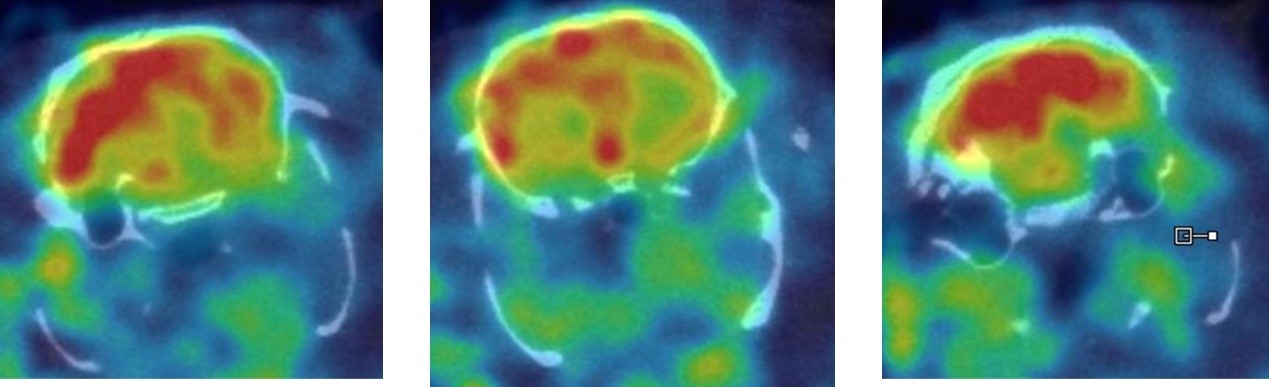

1、神经系统SPECT成像

大鼠脑部SPECT成像:99mTc-HMPAO:脑血流灌注显像剂,用于脑血管疾病,脑外伤,癫痫,痴呆症,脑死亡的诊断;用于精神疾病的脑功能及正常脑生理功能活动的研究。进入脑组织的99mTc-HMPAO构型改变而转变成水溶性化合物,无法再次通过血脑屏障而滞留在细胞内,因此能在脑内长时间滞留。120 MBq,30 min uptake,30 min SPECT。